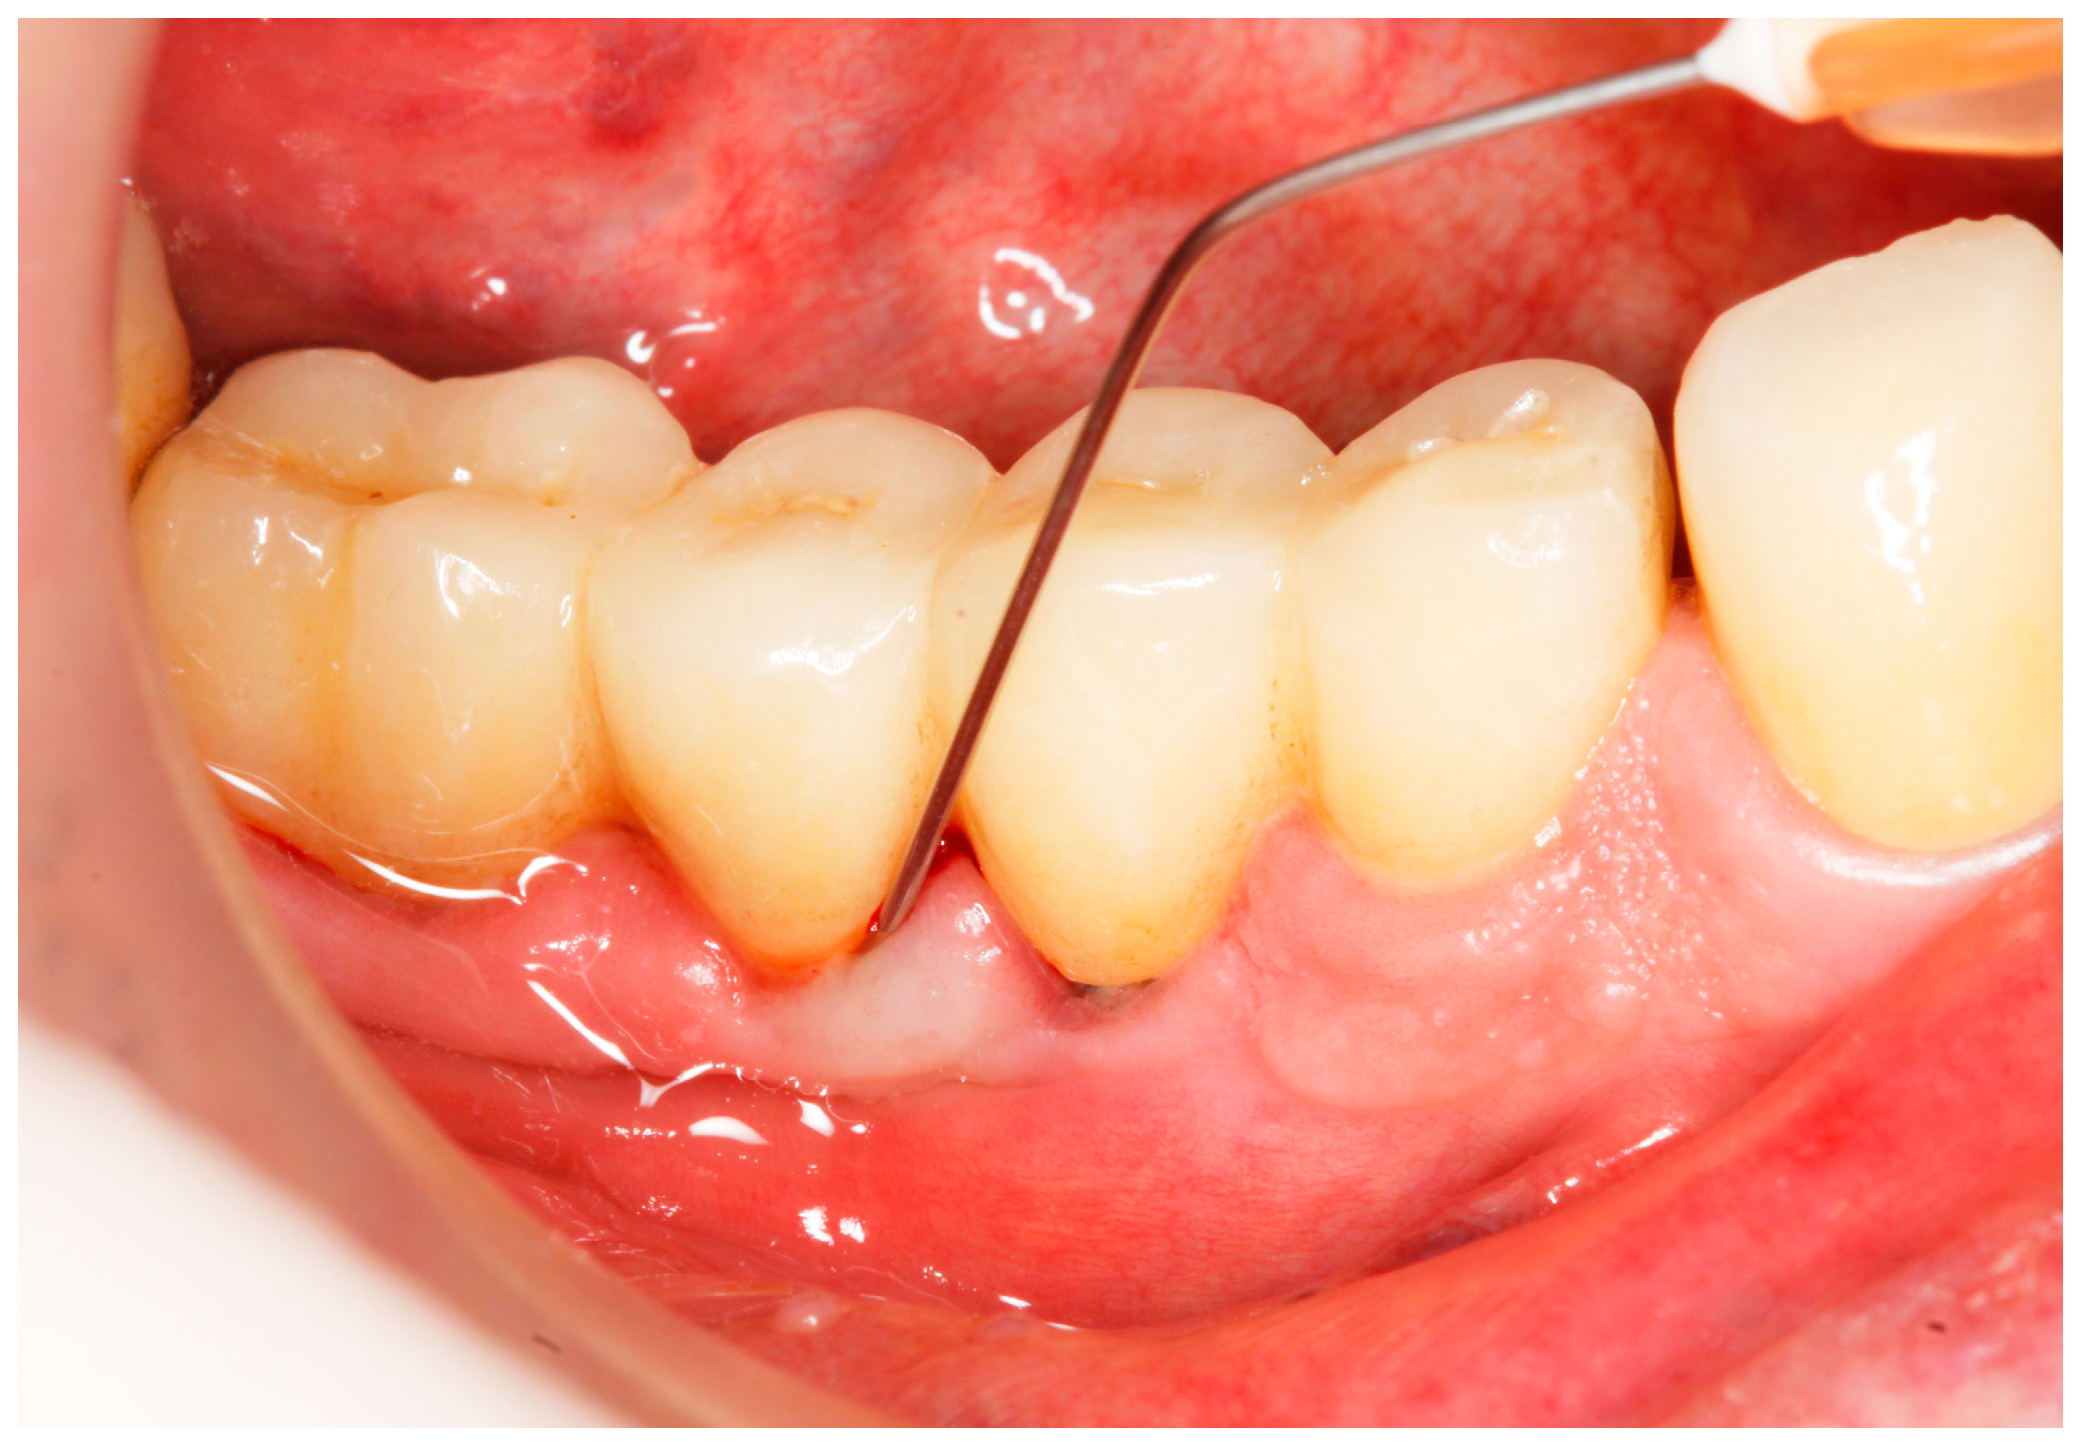

2.6. Clinical Examination

- Implant probing pocket depth (PPD) was measured from the mucosal margin to the bottom of the probable pocket and evaluated at six sites per implant (i.e., disto-buccal, mid-buccal, mesio-buccal, mesio-lingual/palatal, mid-lingual/palatal, disto-lingual/palatal);

2.8. Treatment Procedures

- PMPR, individualized OH recommendations, for entire dentition/implants;